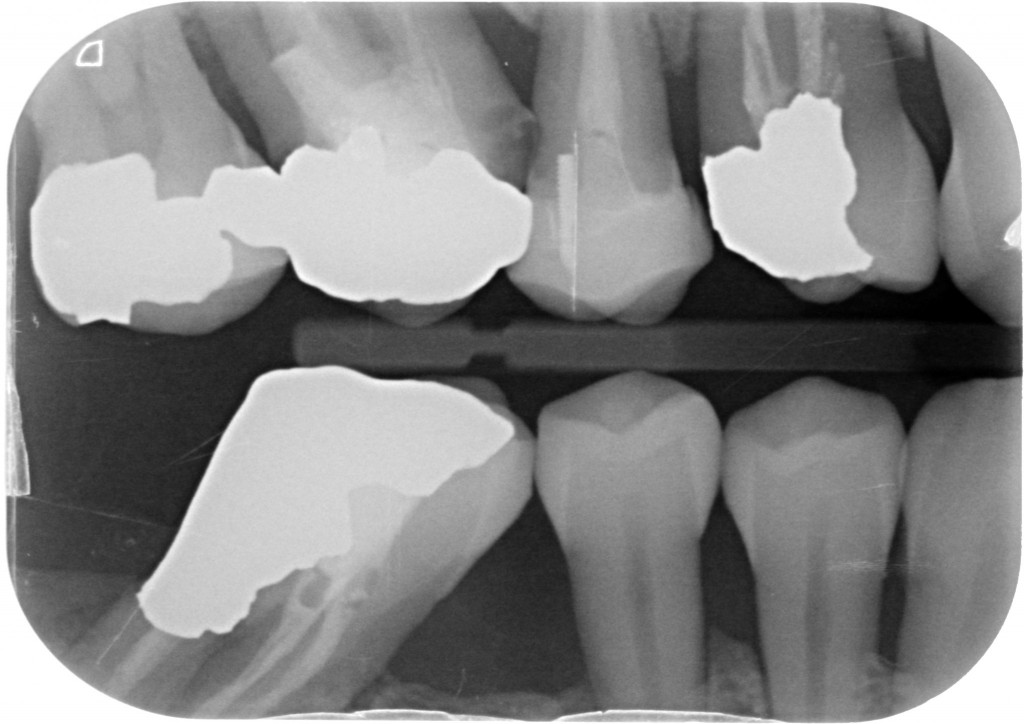

Se invadere l’ampiezza biologica massacra l’osso e genera tasche spiegami perchè in queste due rx scattate a 4 anni di distanza tra loro, l’osso distale al 4.7 mesializzato, che sarà da estrarre per altri motivi, sia sempre uguale, con un risentimento legato alla carie primaria che c’era stata verosimilmente decenni prima…?

Come puoi vedere dalle immagini qui sotto, il caso che ho mostrato nella rx precedente a 4 anni di distanza mostra che nè l’osso nè la papilla risentono di questo terribile insulto…